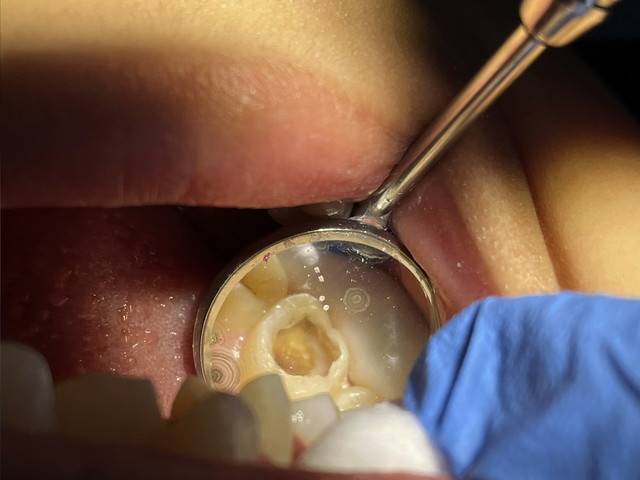

The sight of the four-year-old's dental condition was distressing, as the majority of his baby teeth had been reduced to stumps, and more than 10 teeth faced irreversible cavity problems, leaving no viable option for saving them.

As a final intervention, the dentist had to extract all of the boy's milk teeth to prevent severe inflammation of the gums or tooth roots, averting potential complications such as swelling, suppuration, and susceptibility to various diseases.

"This boy is suffering from severe early childhood caries which requires all his teeth to be extracted earlier than they should be. Each baby tooth will fall in its own time before permanent tooth growth. For example, front teeth fall between the ages of six and seven, depending on the tooth structure.

"When they have to be extracted as early as two or three years before the growth of permanent teeth, these children will find it difficult to eat, resulting in disrupted growth due to lack of proper nutrition," explained Dr. Muhammad Nazmi Abdul Majid to Bernama.